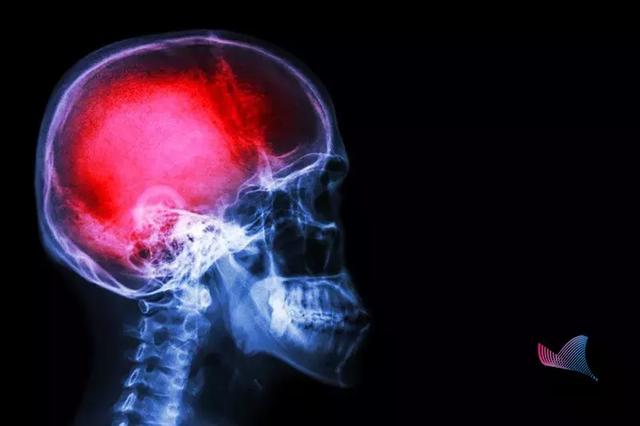

中風

第一殺手,是造成中國人壽命損失的第一大病因。據WHO數據顯示,我國腦卒中的發生率位居世界第一。

我國每年腦卒中發生病例500余萬,其中約有196萬人死亡。

每6.2秒就有一人發生,每16秒就有一人死亡!腦卒中已成為我國居民死亡首要因素。更可怕的是,中風不僅僅是老年人的專利,在我國

腦卒中,又稱中風,很多人對中風的認識只是停留在患者會口眼歪斜、口齒不清。

當附著在血管壁的栓子脫落,堵塞腦部血管時,形成缺血性中風。而當腦血管破裂,顱內出血時,就會形成出血性中風。